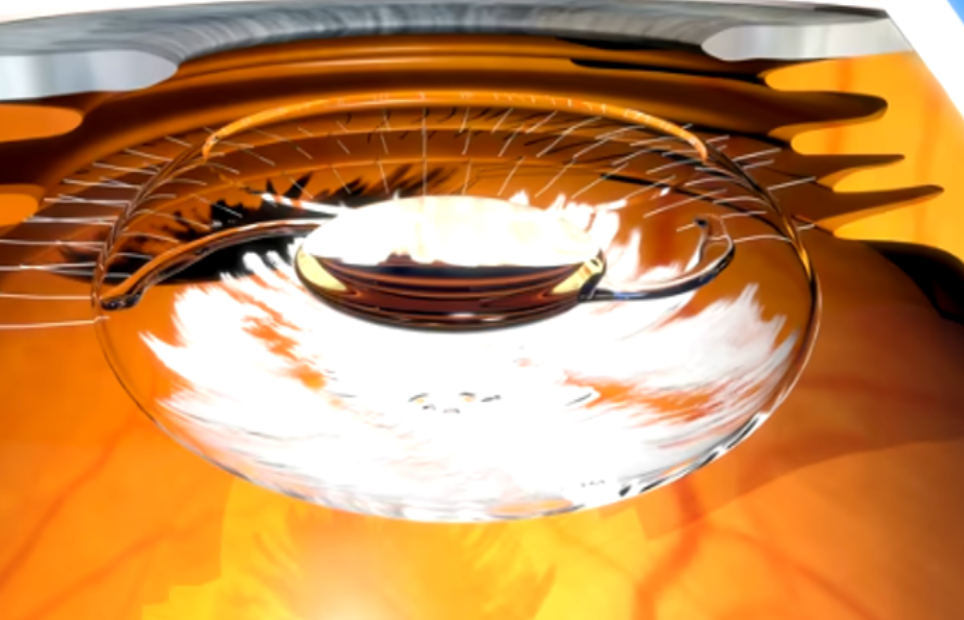

Follow-up Breast Exam 30 minutes

Breast Screening 20 minutes

This screening can help identify abnormalities such as tumors, cysts, or vascular issues at an early stage, potentially improving treatment outcomes. Our general screening exams include: breast, thyroid, kidneys, liver, spleen, aorta, pancreas, and calf veins.